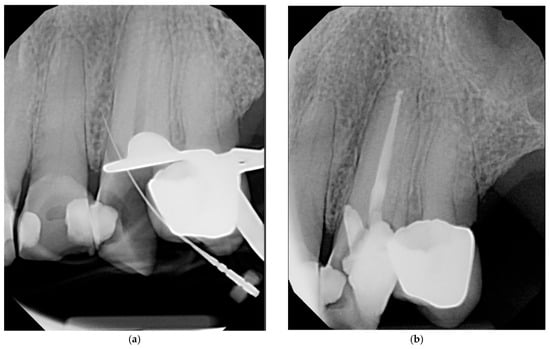

4.9. Repair Materials

Figure 3. Periapical radiographs illustrating the same crestal perforation on tooth #11: (a) periapical radiograph illustrating perforation intra-operatively; (b) periapical radiograph illustrating perforation immediately after repair using Bio-C repair putty.